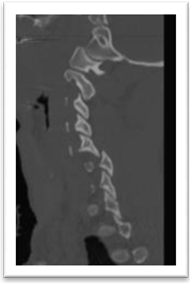

Female patients 25 years old was felled from height with modified Frankel’s grade D and DFI stage 2. Closed skull traction was failed. Posterior cervical approach, unlocking of the facet, bone fusion and lateral mass fixation with rods and screws (Figure 2).

Figure 2. Showing case 2 presentation. (a) Pre-operative CT (b) pre-operative CT with bone window (c) post-operative plain X-ray lateral mass rode and screws fixation and fusion.